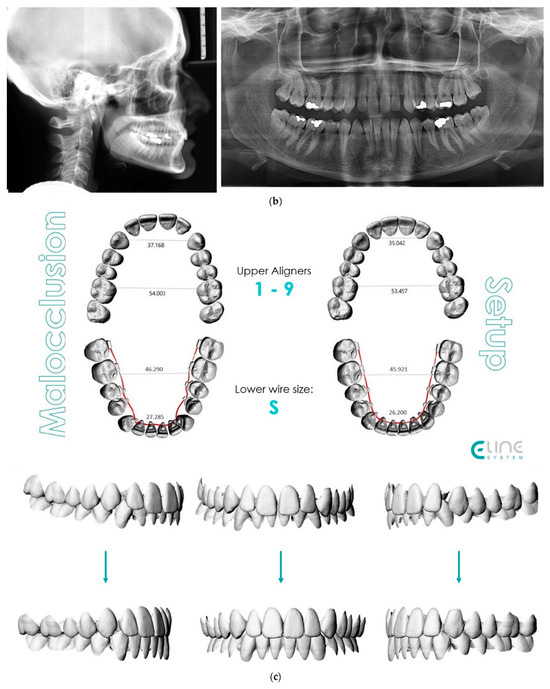

- Case 2: Class III with deep bite

4.2. Case 2: Class III with a Deep Bite